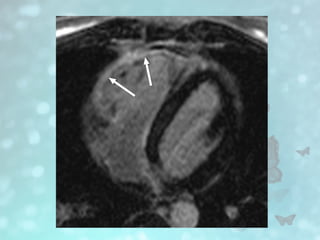

• #19 True fast imaging with steady-state precession MR images in long axis show right ventricular aneurysm, with corrugated right ventricular wall (accordion sign), and dyskinesia.